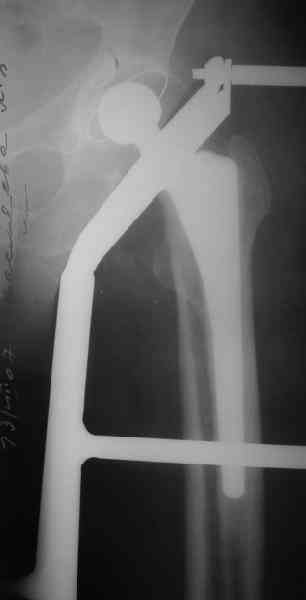

При этом переломе никакие гвозди не подойдут, поскольку линия раскола идет аж до верхушки большого вертела.

1. Представляющей наибольшую ценность из представленной информации следует считать фасные снимки №3и №4 (если считать по порядку). На снимке №3 не видны ни проксимальный отдел бедра с зоной (линией) перелома - наложение тени, ни дистальная зона (линия) перелома - область не захвачена. Снимок №4 демонстрирует дистальную линию перелома, но не показывает уровень конца ножки эндопротеза. В таких сучаях как способ можно выполнять снимок "с метками" - чтобы при при наложении снимков на негатоскопе иметь целостностное представление о всём сегменте от тазобедренного до коленного суставов.

2. Не совсем так. Перелом В2 (по C. Duncan и B.A.Masri, 1995) - перелом на уровне ножки эндопротеза или непосредственно дистальнее её конца с нестабильностью ножки, но хорошим качеством кости проксимального отдела бедра. Как известно, по статистике - наиболее часто встречающийся тип перипротезного перелома при первичном эндопротезировании. Очевидно - продольное раскалывание проксимального фрагмента в данном случае вызовёт нестабильность ножки.

Вот фрагменты этих снимков с более различимыми областями интереса.

Видимо, тут надо добиваться точной репозиции этой спирали вдоль протеза, чтобы воссоздать ложе для ножки.

Недостаток такого ведения - осложнения , связанные с длительным постельным режимом, которые могут привести к смерти

2.Оперативный метод лечения. Выбор вида фиксации зависит от стабильности бедренного компонента.Излишне напоминать, что операция должна быть проведена так, чтобы не было необходимости повторных вмешательств. Вы имеете дело с переломом, проходящим практически через всю длину протеза и заканчивающимся дистальнее цементной пробки. Такие переломы ведут к нестабильности бедренного компонента. Хотя окончательное решение о стабильности можно принять только на операционном столе.